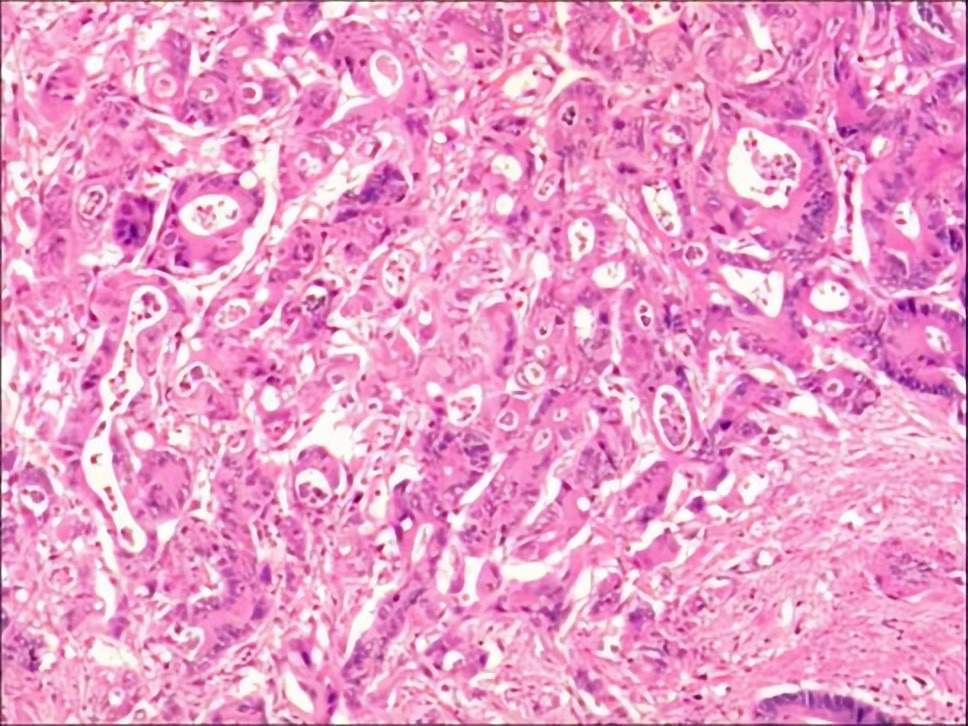

2017.11术后病理

1.(左肝外叶)结合HE形态及临床病史,符合肝转移性腺癌伴灶区坏死(肠癌 原发),送检标本之断端未见癌累及。2.(胆囊)慢性胆囊炎,切片未见癌累及。3.(吻合口原发肿物)肠中分化腺癌(肿物大小:4x3x1.5),癌组织浸及肠壁全层,切片未见明显神经及脉管浸犯;另于肠系膜检出淋巴结9枚,其中2枚见癌转移(2/9)。

▲肝脏病理。

▲吻合口原发肿物病理。